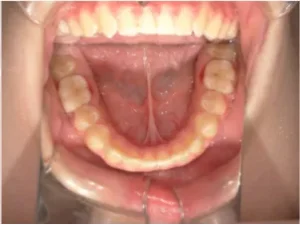

toshi_05_06